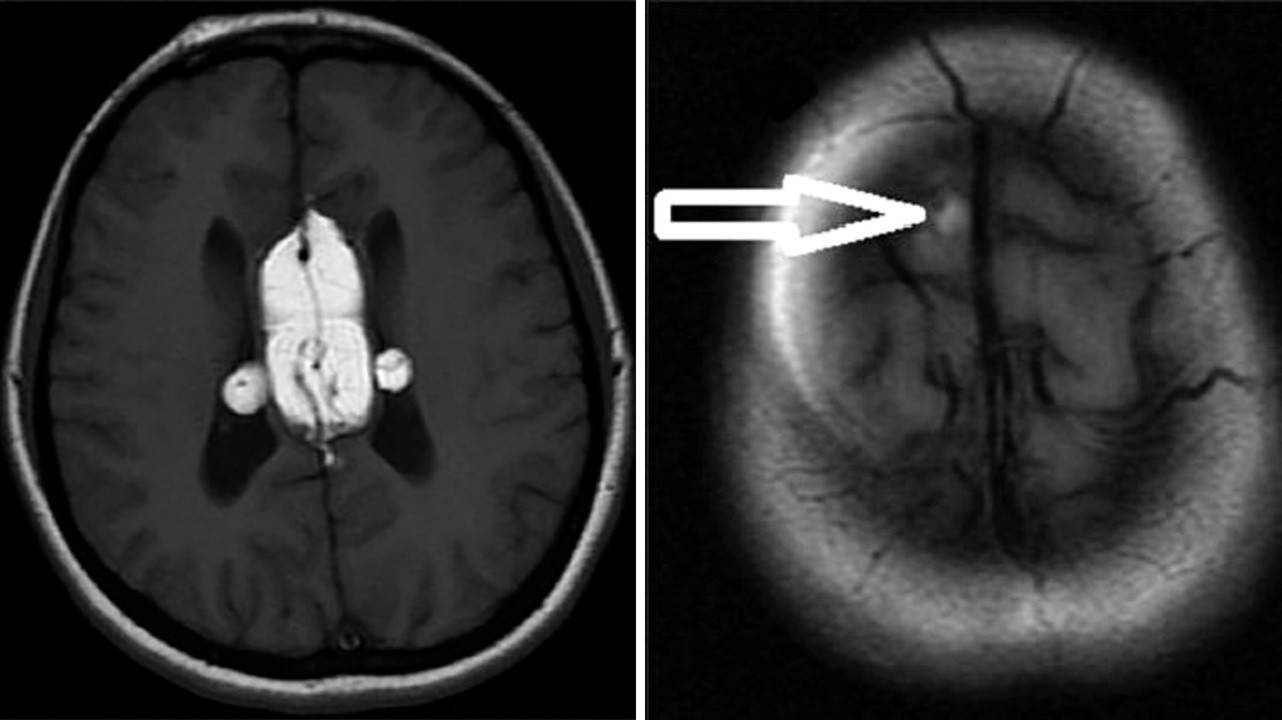

Липомы головного мозга также выявляют случайно, когда у пациентов старшей возрастной группы проводят МРТ или КТ мозга по каким-то другим причинам, например, при нарушении когнитивных функций, эпилепсии. Липомы могут быть обнаружены в любом отделе мозга, тем не менее 50% – это перикалозальные липомы, в свою очередь 45% которых ассоциированы с агенезией мозолистого тела. 25% составляют липомы квадригименальной цистерны и 15% – липомы супраселлярной цистерны. Так как липомы мозга не имеют симптомов, хоть и часто сочетаются с какими-то пороками, например, агенезией мозолистого тела, то и лечения они не требуют. Хирургическое лечение сопряжено с большим риском осложнений и не имеет никаких преимуществ. Если возникают гидроцефалия или судорожный синдром, то лечение проводят по общим правилам.

Липома мозолистого тела головного мозга. Фото: Journal of neurosciences in rural practice / Open-i (Attribution-NonCommercial-ShareAlike 3.0 Unported)